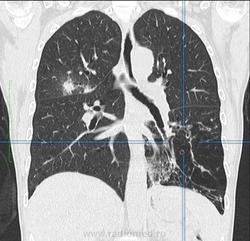

Женщина 50 лет, поступила в стационар с жалобами на субфебрилитет, постоянно рецидивирующие бронхит и пневмонию на протяжении 2 лет. Выполнена ФЛГ - подозрение на сегментарную инфильтрацию в верхней доле правого легкого, повышена воздушность нижней доли левого легкого.Выполнена КТ - с чем бы Вы дифференцировали процесс, коллеги?

Выложил ключевые изображения, толщиной 5 мм, легочное окно, Kernel 90. Если требуется DICOM - выложу позже

вообще то это зона фиброателектаза с тракционными бронхоэктазами(слева ),справа в верхней доле многогоузловое с утолщенным интерлобулярным интерстицием переходящим на междолевую плевру (локальное утолщение ее ),признаков тракции ее не обнаружено,на фронталах по периферии крупного узла утолщенный интралобулярный интерстиций(локального лимфостаза не обнаружено )-вообщем все старое .хотелось бы на все в медиастинальном окне посмотреть ,а так специфику с неспицификой

Да ладно Вам,какой же это фиброателектаз?Я бы скорее подумала о секвестрации.В артериальную фазу при контрастировании можно увидеть аберрантный сосуд,связанный с аортой .Заодно решите проблему справа.Для более точной диагностики посмотрела бы все исследование,т.к.представленных сканов недостаточно.Какая-то кистозная дисплазия в S10слева имеется,похоже и на бронхоэктазы.Вот основные направления,над которыми надо работать.

при всем уважении к вам коллега не соглашусь с вами т.к.объем то нижней доли слева уменьшен(первый скан это 100% показывает ) -четкие вогнутые контуры на фоне сближенного легочного рисунка ,говоря даже ренгенологическим ,а не радиологическим языком +тракция бронхов неменуемо подталкивают на использованный мною термин (пусть будет фиброгиповентиляция -словами можно играть сколь угодно)-но механизм я объяснил.возрастные нормативы всегда беру при постановке диагноза +анамнез не противоречит синдрому.при секвестрациях объем не уменьшен ,да и всегда есть четкая солидная часть.мальформация у нас 3 типов и все не подходят ,да и где гипоплазия левого легкого,с уважением федя.

У больной бисегментарная инфильтрация в верхней доле правого легкого. Какой этиологии пока неизвестно, возможно и TB (клиника очень стертая, сдали мокроту на КУМ).

Насчет изменений в нижних отделах - то описал их как диффузные структурные изменения прам-пам-пам с развитием центрилобулярной эмфиземы.

Там и циллиндрические бронхоэктазы, и центрилобулярная эмфизема. В обоих легких, больше в левом. Бронхиолы сильно расширены, практически до субплевральных отделов, причем бронхоэктазы есть не только в нижних отделах, но и в верхних. На последней 3Д реконструкции неплохо отображено бронхиальное дерево. оно патологическое.